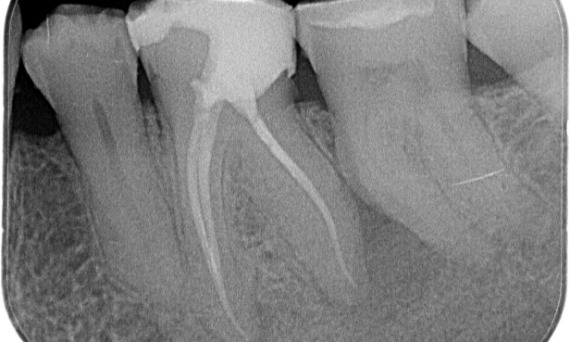

Después: En este caso, se eligió TruNatomy para permitir un enfoque apalancado en las caries y un enfoque en la conservación de la dentina pericervical, especialmente en el aspecto mesial donde el diente tuvo una restauración más mínima.